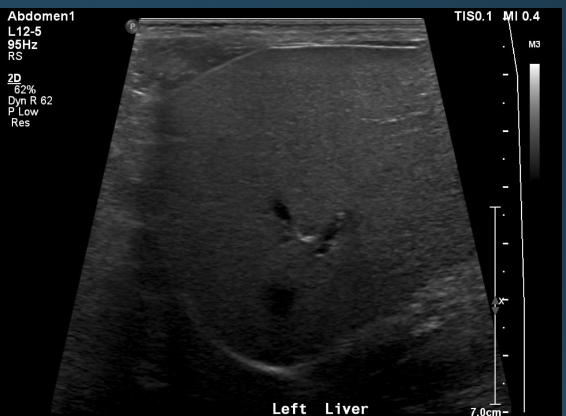

What is shown in these images?

normal ultrasound of the liver